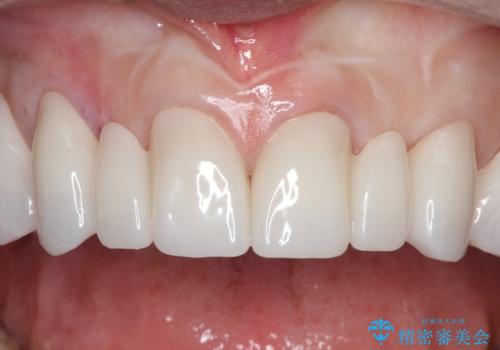

【オールセラミッククラウン】前歯を綺麗にしたい。

- 前歯の被せもののやりかえを主訴に来院されました。

前歯の歯茎から膿も出ていたため、歯内治療を行なったのち修復を行なっております。

根管治療および外科的歯内療法を行なってから被せものの処置を行なっております。